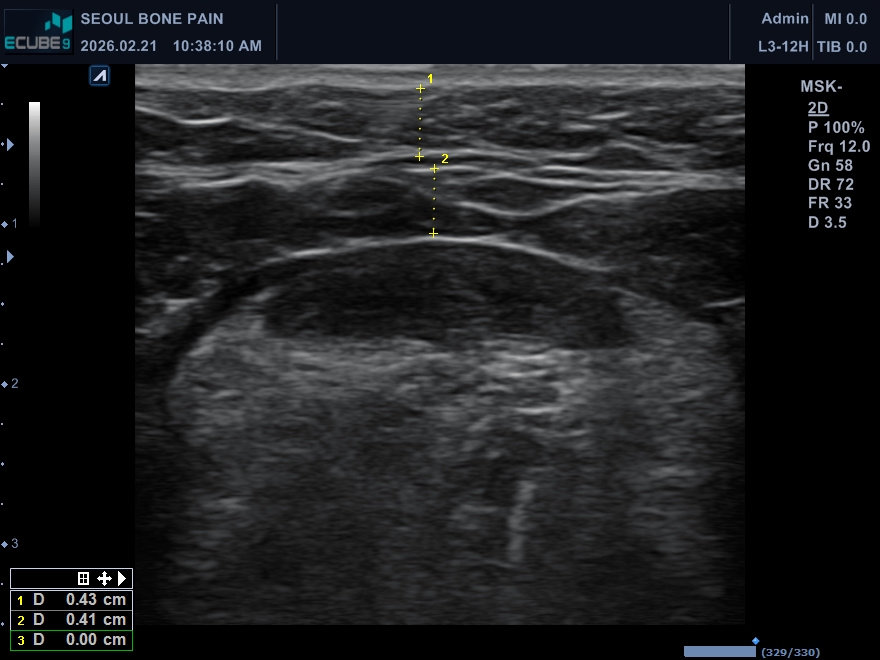

▲ 실제 턱밑 초음파 검사 사진

가운데 근육을 중심으로 위, 아래 두 층의 지방이 분포

위 초음파 사진을 보시면 근육층(활경근)을 경계로 위쪽의 피하지방과 아래쪽의 속지방 두께가 거의 1:1 비율인 것을 확인할 수 있습니다.

즉, 겉에 있는 지방만 아무리 뽑아내도 근육 안쪽의 속지방이 그대로 남아있다면 이중턱은 결코 드라마틱하게 개선되지 않습니다.